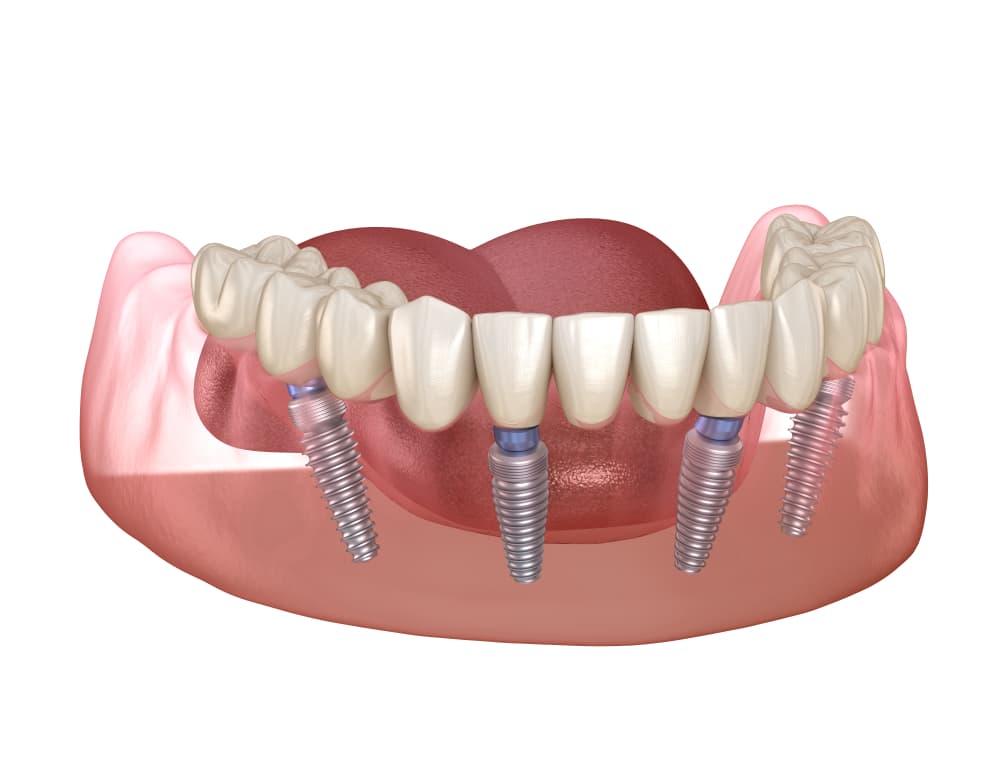

בעבר האמינו שלא ניתן לוותר על השתלת עצם כדי לאפשר קליטה נכונה של השתלים, אולם בשיטת All on 4, ניתן להתקין כמה כתרים על גשר מאוחד שנתמך על ידי ארבעה שתלים בלבד. בדרך זו, ניתן לקבע את הכתרים בצורה טובה ובמקרים רבים גם ללא הליך מקדים של השתלת עצם על כל המשמעויות שלו.

באופן עקרוני, שחזורים של שיניים מורכבים משני חלקים מרכזיים. השתל הוא בורג שמוחדר לתוך עצם הלסת ומקבע את הכתר שמחובר אליו ומחליף את חלקה הנראה לעין של השן. לכן, חלק מהאנשים עשויים לחשוש מהעובדה שבטיפול הזה מלבישים שורה של כתרים על ארבעה שתלים בלבד, במקום לחבר כל כתר לשתל משלו, כמו שנהוג לעשות. עם זאת, חשוב להדגיש כי גם בשיטה הזאת, שחזורי השיניים מתנהגים כמו שיניים רגילות לכל דבר וניתן להשתמש בהם בדיוק כמו בשיניים המקוריות בלי לחשוש.